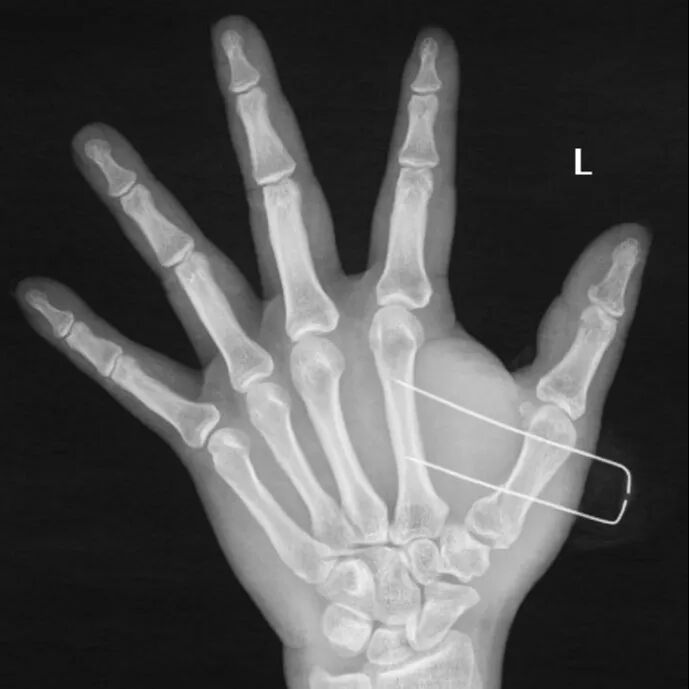

患者是39歲男性,因摔倒導致左手第一掌骨基底部骨折。

手術前左手正斜位片

手術后次日復查左手正斜位片